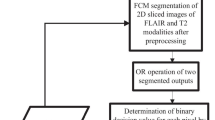

Brain tumour is a lump of tissue produced by uncontrolled growth of cells in the human brain. Automated and accurate detection of brain tumour is important for robotics based surgery operation. The proposed method enhances the accuracy, sensitivity and specificity of automated brain tumour detection by adopting an accurate two phase method of detection. The method segments the Axial plane slices of Magnetic Resonance image in its first phase. In the second phase, binary decision values representing the presence or absence of tumor cells on each pixel locations are projected into 3D space to obtain the 3D tumor. Contrast Enhanced fuzzy c-means (CEFCM) clustering method is used to segment the 2D tumor regions from MR image slices due to its high accuracy. The decision values obtained from the segmented image for each pixel locations are mapped into 3D space using Pixel based voxel mapping technique (PBVMT). Average accuracy (Dice overlap coefficient) and average sensitivity of detection are measured with respect to the given ground truth of the image of BRATS 2013 dataset. The overall accuracy, sensitivity and specificity of detection are found to be 0.948, 92.14% and 96.97% respectively.